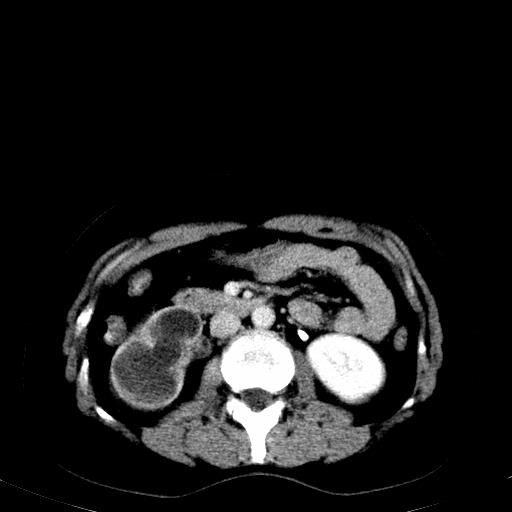

右肾多发囊肿,左肾、左输尿管结石

右肾重度积水,以肾盏积水明显,有分隔,上段输尿管轻度扩张,管壁增厚,考虑肾结核可能,请结合尿检查,胸部拍片排除肺结核。

右肾重度积水,建议ct向下扫描或逆行造影,左肾及左输尿管结石 .

1)不排除右肾结核可能。2)左肾及左输尿管上段结石?

左肾不像是结石吧,是不是做过造影啊

左肾哪里有结石???

左肾不是结石,是造影后改变.右肾积水,功能仅存.